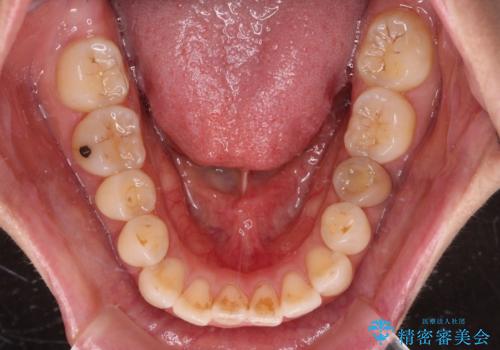

【モニター】飛び出した上顎前歯 補助装置を併用したインビザライン矯正治療

- 上下前歯が非接触となり、前方に突出していることを気にして来院された患者様です。

上下の前後差が大きいため、インビザライン単独での上顎歯列移動は困難と判断し、補助装置により上顎歯列を後方移動させ、その後インビザラインにて仕上げていくこととしました。

また、舌の突出癖が非接触の原因の大きな要因と考えられるため、舌のトレーニングをしっかり行っていくよう指導しました。